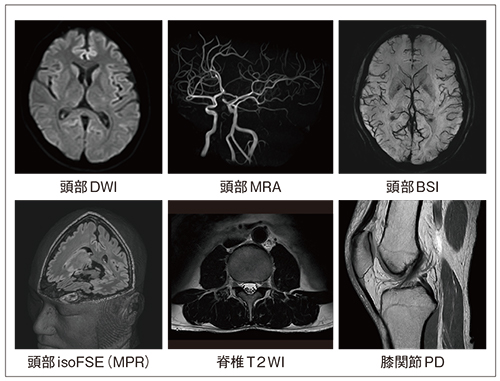

ECHELON Smartの画像例

図5に画像例を示します。ひずみの少ない拡散強調画像や高精細なMRA画像は,高い基本性能を示しています。BSIは磁化率の影響を強調した画像です。EPIシーケンスをベースとしており,高速撮像が可能です。isoFSEは3Dのアイソボクセル撮像機能で,可変フリップアングルを利用して高速に高精細3D画像を得ることができます。アイソボクセルのため,MPRにより任意断面を自由に再構成可能です。

さらに,脊椎の神経描出や膝関節の高精細画像など,全身にわたり高画質撮像を実現しています。

図5 画像例